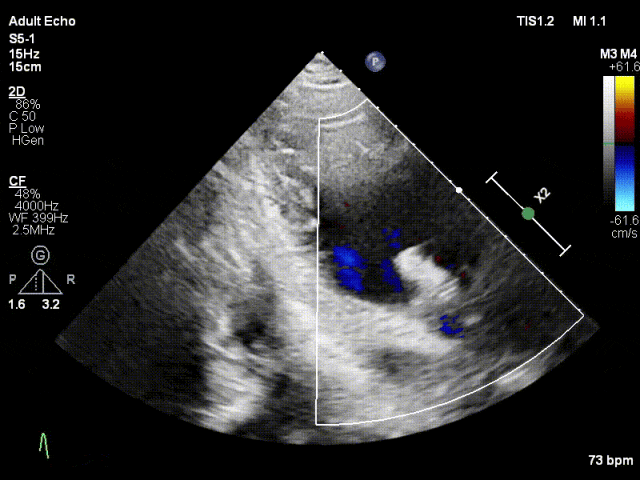

TTE上彩评估无明显反流

L侧残余微量功能性反流

TMPG:1mmHg

肺静脉逆流消失